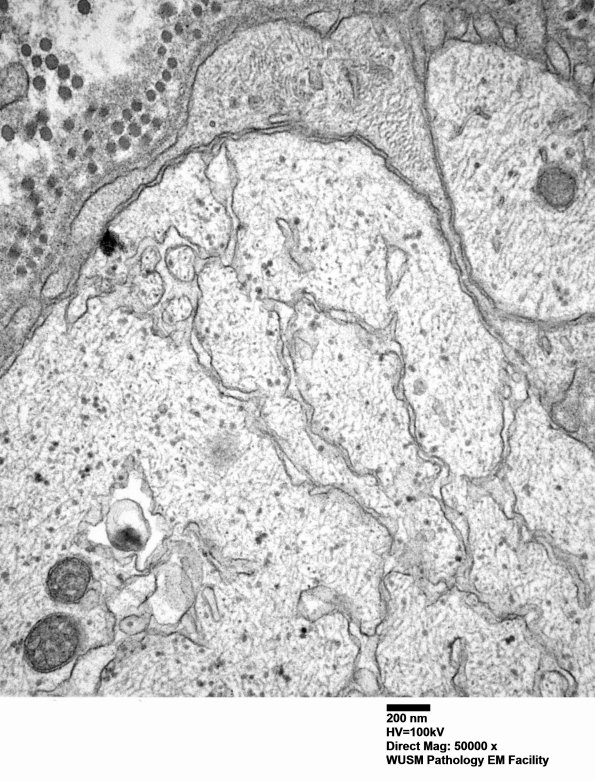

Washington University Experience | PERIPHERAL NEUROPATHY | 6 AXONAL DEMYELINATION (BASIC PROCESS) | 5B5 (Case 5) EM 008 - Copy

Higher magnification of image #5B4. (electron micrograph)